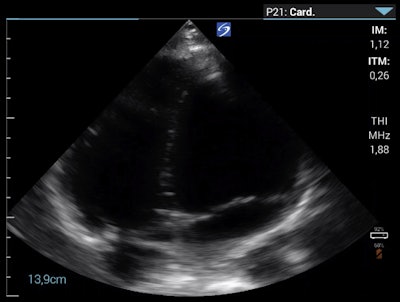

To investigate pulmonary embolism (PE) as a potential cause of the clinical deterioration, the researchers performed point-of-care echocardiography (parasternal long axis, parasternal short axis, and apical four-chamber view). These views showed a slightly enlarged right ventricle/left ventricle ratio greater than 0.6, which allowed them to exclude a large, central PE.

Apical four-chamber view on the morning of day eight.Wipplinger said that although they could not exclude peripheral PE, the patient did not have typical symptoms, such as chest pain or a cough, which made them question peripheral PE as a differential diagnosis. They interpreted the right ventricle enlargement as an indirect sign of pulmonary hypertension that was most consistent with HAPE.